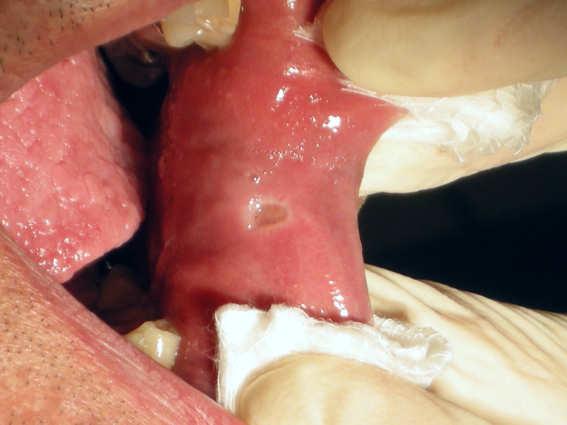

Cheek fibroma

Dr. Valter Pirazzoli

Laser Setting , Diode Laser 810nm

Power: 2,0 Watt,

CW

Fibre 400 micron